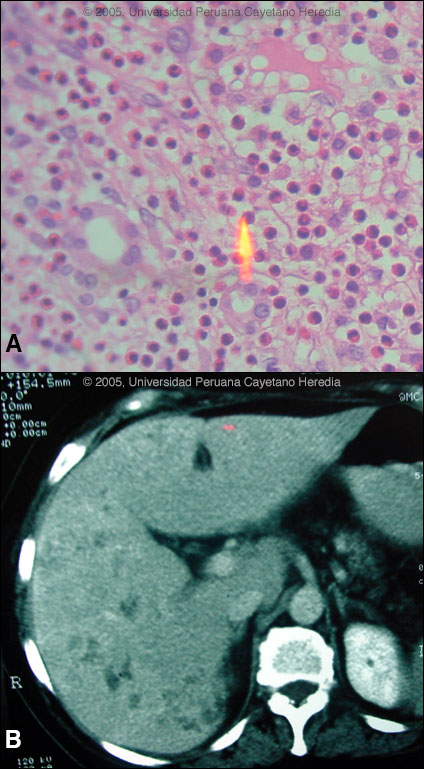

Epidemiology: From agricultural community in Ancash high in the Andes. Diet based mainly on vegetables and grains. No TB exposure. No significant ethanol intake. Physical Examination: (on transfer to Lima): Fever, RUQ rebound (positive Murphy's sign). Chest clear. No splenomegaly or lymphadenopathy. Stool heme negative. No rash. Laboratory Examination: Hb 11.5. WBC 16,500 with 25 neutrophils, 4 bands, 10 lymphs and 63 eosinophils. Both transaminases and alkaline phosphatase 3X normal. Bilirubin 1.8. Negative blood cultures. Negative serology for typhoid and brucella. Negative stool for O & P. Abdominal echo with 1 small stone in the gall bladder with no inflammatory changes. The patient was admitted to the surgical service and given intravenous antibiotics for 3 days without resolution of fever or symptoms. At laparoscopy, the gall bladder was normal but the liver surface was noted to be studded with abscesses or metastases and a full laparotomy disclosed only the lesions diffusely on the surface of the liver. The patient remained febrile with leucocytosis and eosinophilia despite 2 weeks of post-operative antibiotics. The liver biopsy is shown in Image A and a CT scan of the liver taken 1 week post-operatively is shown in Image B.

Diagnosis: Fasciola hepatica infection, acute phase.

![]() Discussion: Further examination of omental tissue taken at the original surgery showed larvae of F. hepatica [Image C]. IgG FAS2 ELISA [Trans R Soc Trop Med Hyg. 1999 Jan-Feb;93(1):54-7] was positive for Fasciola hepatica at 3.2 OD units (Normal <0.2). Fasciola hepatica is a trematode (fluke or flatworm) in which the mature adult parasites inhabit the large biliary ducts. The adults are from 1 to 3 cm long and attach to the biliary epithelium by a single ventral sucker [Image D from our case files shows an endoscopic view of an adult in the common bile duct]. In the absence of direct visualization, characteristic eggs can be seen on stool examination, but more often patients present in the early migratory phases of infection prior to maturation of the worm and the onset of egg-laying. Specific serology is test of choice. As with all other trematodes, Fasciola hepatica requires a snail intermediate host. Eggs produced by the hermaphroditic adults pass with the feces and hatch, releasing larvae in fresh water. After passing through a snail, mature cercariae emerge and rapidly encyst on various kinds of aquatic vegetation such as watercress. After ingestion by a human or animal definitive host, the metacercariae excyst in the duodenum and larvae pentetrate the intestinal wall and subsequently migrate directly into the liver via Glisson's capsule. The larvae then embark on a destructive migratory process through the hepatic parenchyma for 3 to 4 months until they reach large biliary ducts where they mature to adults. The distribution of Fasciola hepatica is cosmopolitan, but is by far the most common in sheep-raising areas where herbivores are common definitive hosts. Heavily infected sheep develop "sheep liver rot". Other important definitive hosts are goats, cattle, horses, llamas, vicunas, and camels. The contiguous altiplano regions of the Peruvian and Bolivian Andes are highly endemic, with human prevalence rates of as high as 67% in some villages. Egypt, Cuba, and Northern Iran are also highly endemic. Cooking, which would kill the metacercariae, dramatically changes the flavor of watercress and the population is reluctant to adopt this simple measure. Our patient regularly ingested watercress. Clinically, the disease can be divided into acute and chronic phases. During the acute phase, migrating parenchymal larvae cause fever, eosinophilia, right upper quadrant pain and especially significant anorexia. Vomiting and weight loss of 20 kg or more may develop, which usually abates when the larvae mature to adults. The adult flukes in the biliary tree are generally asymptomatic but some patients develop chronic manifestations including right upper quadrant pain, nausea, vomiting, and hepatomegaly. Eosinophilia and abnormal liver function may develop but are less common than with acute disease. Adult flukes may cause hyperplasia, desquamation, thickening, and dilatation of the bile ducts. Malignant degeneration and cholangiocarcinoma such as results from chronic infection with the oriental liver fluke Clonorchis sinensis has not been reported with Fasciola hepatica. The differential diagnosis of hypereosinophilia with accompanying destructive hepatic lesions is limited. Toxocariasis causes hypereosinophilia with hepatomegaly but the pathology results from small granulomas around individual non-migrating larvae and not the large destructive tracks as was seen on the CT in our patient. Fasciola hepatica is the only trematode infection for which praziquantel is not the drug of choice. WHO has put the veterinary anthelmintic triclabendazole (Novartis) on its essential drugs list and has declared it the drug of choice despite the fact that human preparations are registered in only 2 countries. In Perú, the veterinary preparation is readily available and used. In the U.S. and many other countries the veterinary preparation can be obtained by special release from the manufacturer. The usual dosage is 10 mg/kg with a meal. Many practitioners repeat the dosage 12 to 24 hours later. In our institute the cure rate is 96% (A. Terashima, unpublished). Our patient was treated with a single 2-day cycle of triclabendazole 10 mg/kg/day with symptomatic improvement and no fever 2 weeks after treatment. WBC at follow-up was 7,800 with 20% eosinophils. Follow-up to Gorgas Case of the Week 2003-12 Only case reports but no series of sequential CT scans of the acute phase of fascioliasis have been published. Lesions are irregular, hypodense, sometimes oblong and branching. One recent published case shows serial CT scans over a 9-month period demonstrating changes in position, and shape of lesions over time, as would be consistent with the destructive nature of the migrating flukes [N Engl J Med. 2002 Apr 18;346(16):1232-9]. In a case seen by Gorgas participants in 2003 [Gorgas Case 2003-12] we demonstrated that in a case of massive fascioliasis, the destructive inflammatory tracks made by migrating larvae persist radiologically and histologically for months even after apparent parasitic cure. We have recently seen this patient in follow-up 2 years later and now report hepatic calcification as a sequelae of acute fascioliasis [Image E]. In addition, hepatic transaminases, alkaline phosphatase and bilirubin have been normal for the past 1 year, stool O & P remains negative, and the patient is asymptomatic. However, an eosinophilia of 8% persists.